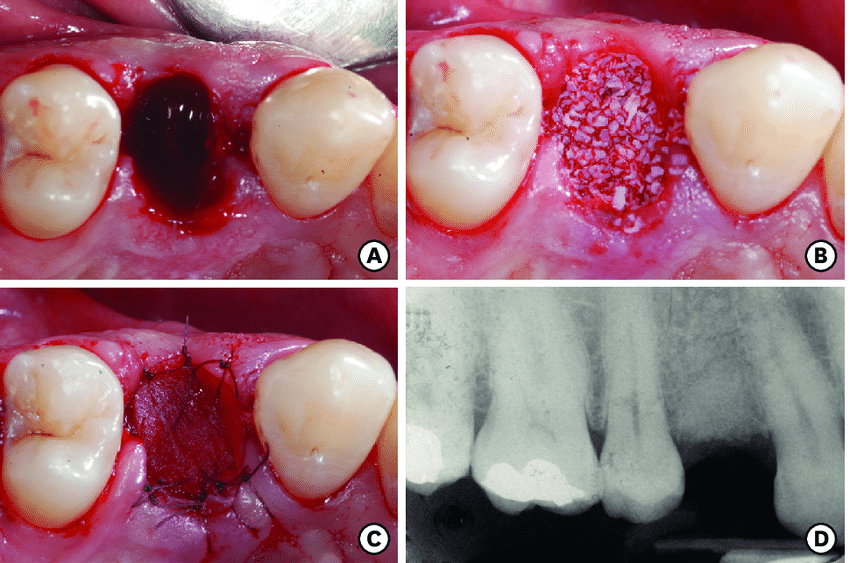

Before and After Images

Our Surgical Extraction Experiences

A tooth that has not erupted properly and is stuck beneath the gum line or bone. Wisdom teeth (third molars) Pain, swelling, infection, damage to adjacent teeth. Surgical extraction involves making an incision in the gum and sometimes removing bone to extract the tooth.

Surgical extraction is a procedure to remove teeth that cannot be easily accessed. This may be due to teeth that have not erupted fully or are impacted. The procedure involves making an incision in the gum to access and remove the tooth.

During the surgical extraction, our skilled dentists will administer local anesthesia to numb the area. An incision will be made in the gum to access the tooth, which will then be carefully removed. The site will be cleaned and sutured to promote healing.